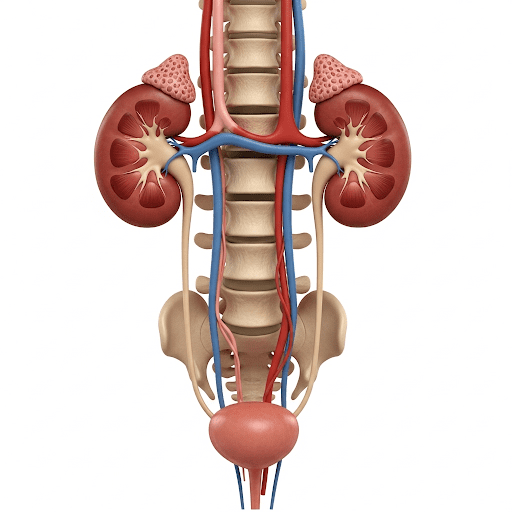

BỆNH HỆ TIẾT NIỆU

- BỆNH HỆ TIẾT NIỆU

Chế độ ăn uống và tập luyện cho bệnh nhân suy thận theo từng giai đoạn

Suy thận mạn tính (CKD) là tình trạng chức năng lọc của thận suy giảm dần, được chia thành 5…

Suy Thận: Nguyên Nhân, Triệu Chứng và Cách Điều Trị Hiệu Quả

Bạn có biết? Suy thận hiện không còn là “căn bệnh của tuổi già” mà đang ngày càng trẻ hóa…